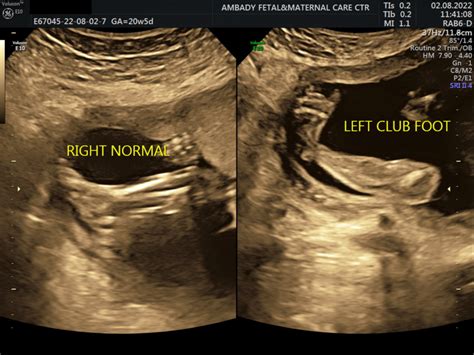

What is clubfoot in babies | Ambady Scan center...